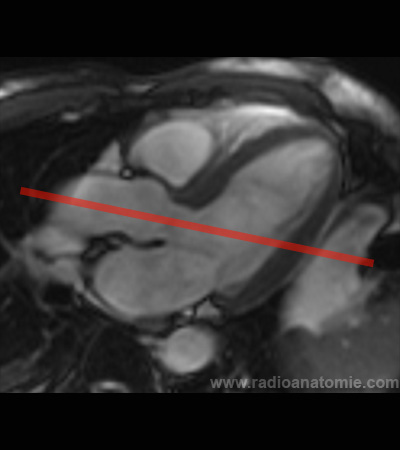

Radioanatomie et plans de coupe en IRM cardiaque

Septum interventriculaire